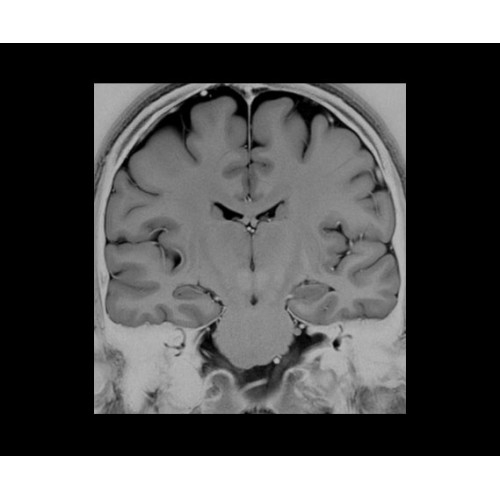

SIGNA PET/MR 3.0T — это гибридная система, в которой совмещаются две принципиально разные технологии — магнитно-резонансную томографию (МРТ) и позитронно-эмиссионную томографию (ПЭТ). Система отличающийся высокой чувствительностью и эффективностью и предназначена для диагностики в области онкологии, неврологии, кардио-васкулярных исследований, исследований воспалительных процессов.

Компания GE Healthcare представляет революционную, полностью интегрированную систему SIGNA PET/MR1, в которой сочетаются времяпролетная технология (TOF) и возможности напряженности магнитного поля 3.0 Тл. Мы поможем вам поднять исследования на более высокий уровень. SIGNA PET/MR позволяет достичь впечатляющей точности и скорости исследований, а благодаря новейшей технологии реконструкции Q.Clear2 качество изображений улучшается в два раза. Кроме того, в систему включен полный набор клинических приложений и гибких катушек для проведения любых видов исследования, открывая для вас возможности визуализации, о которых вы даже не догадывались.

Система SIGNA PET/MR предлагает впечатляющие клинические возможности и открывает доступ к наиболее полным пакетам программных приложений.

Стандартный пакет приложений SIGNA Works позволит вам достичь желаемых результатов в клинической практике благодаря набору высокоэффективных средств визуализации. Программные приложения, входящие в состав данных клинических пакетов, включают широкий спектр контрастов, функции обработки 2D- и 3D-данных, а также возможность коррекции артефактов движения. SIGNA Works предоставляет набор инструментов, необходимых для проведения эффективного клинического исследования.